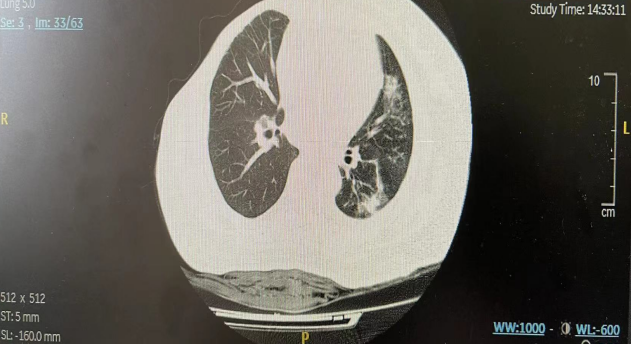

二线治疗前(2022年7月)患者再次出现高热,于外院诊断肺炎(图2)。抗炎治疗3周后,肺炎有所好转(图3),体温恢复。

图2.二线治疗前胸部CT示左肺炎

图3.抗炎治疗3周后胸部CT示左肺炎好转